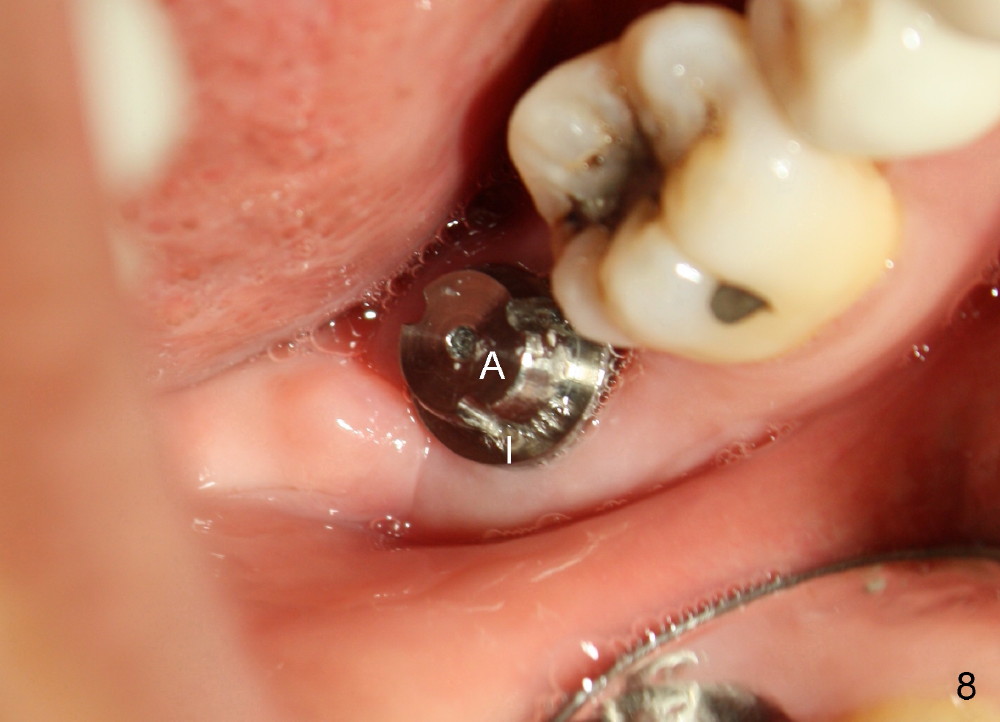

The patient returns 22 days postop (Fig.8-10). The gingiva heals around the implant. There is excess lingual gingiva (Fig.9,10 *), which should recede gradually. Fig.7 is an illustration (from Fig.4) to show how the socket is closed.. A suture is placed (black line) to approximate buccal (black arrow) and lingual (white arrow) gingiva distal to the implant (blue circle).